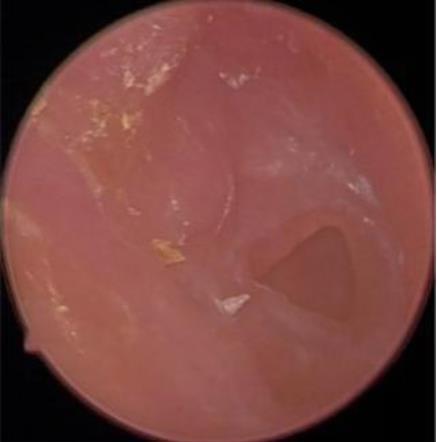

摘要:目的 分析医用生物蛋白胶应用于耳内镜下鼓膜修补术的临床疗效。方法 回顾性分析2022年10月-2023年10月该院收治的60例单纯鼓膜穿孔患者的临床资料,根据手术方法不同,将患者分为研究组和对照组,各30例。研究组术中使用医用生物蛋白胶粘合残余鼓膜和修补材料;对照组术中采用明胶海绵覆盖修补鼓膜。观察两组患者术后的鼓膜愈合情况(鼓膜愈合率、愈合时间、干耳时间和外耳道上下径)和并发症发生情况;于手术前后,采用纯音测听法(500、1 000、2 000、4 000 Hz),测量两组患者气导阈值,观察听力改善程度;采用视觉模拟评分法(VAS)评分,评估患者术后疼痛程度。结果 两组患者术后鼓膜愈合率、愈合时间、外耳道上下径和并发症发生率比较,差异均无统计学意义(P > 0.05)。研究组术后平均气导听阈明显低于对照组,差异有统计学意义(P < 0.05)。研究组术后干耳时间短于对照组,术后第1天疼痛VAS评分明显低于对照组,差异均有统计学意义(P < 0.05)。结论 医用生物蛋白胶应用于耳内镜下鼓膜修补术,可有效地降低气导听阈,缩短干耳时间,减轻患者疼痛,且不增加并发症发生率,值得临床推广应用。